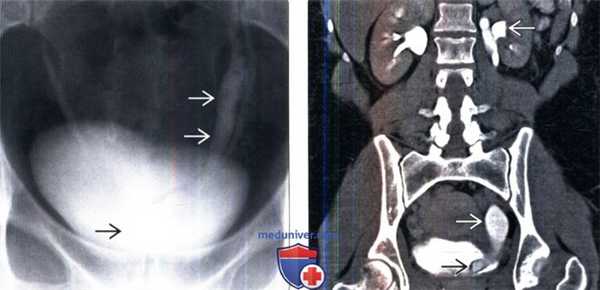

(Слева) Экскреторная урография: полное удвоение левых мочеточников с эктопией уретероцеле в области шейки мочевого пузыря. Дефекты наполнения в расширенной части мочеточника представляет из себя кистозный уретерит.

(Справа) КТ с контрастированием, корональный срез: внутрипузырное уретероцеле с cony ствующим расширением мочеточника и чашечек. Гидронефроз встречается относительно редко и обычно не выражен у пациентов с внутрипузырными уретероцеле.